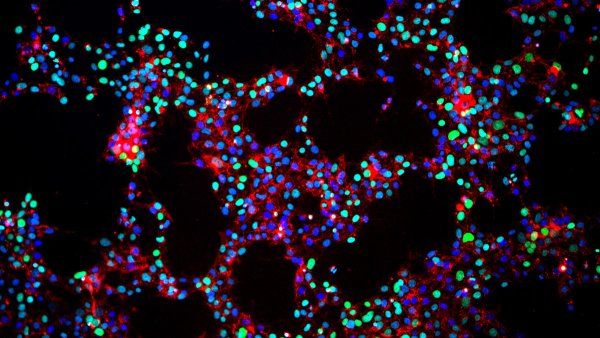

International team of researchers report progress in using stem cells to develop new therapies for Pelizaeus-Merzbacher disease, a rare genetic condition affecting boys that can be fatal before 10 years of age.

Study shows that the adult-to-iPSC conversion process can mutate DNA found in mitochondria, causing mice and humans to reject iPSCs, and stem cell transplants more generally.

In a paper researchers describe a technique that uses a special version of CRISPR developed at UCSF to systematically alter the activity of genes in human neurons generated from stem cells, the first successful merger of stem cell-derived cell types and CRISPR screening technologies.